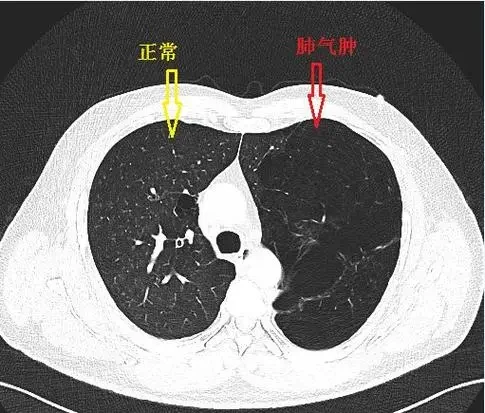

在病理生理层面,慢性支气管炎更多表现为气道炎症和痰液分泌增加,而肺气肿主要特征是肺泡被破坏、气道弹性减退和气流受阻。这些病理改变通过肺功能检查、胸部影像学等可以较为准确地诊断。

辅助检查方面,肺功能检查是慢性阻塞性肺疾病诊断的金标准。通过测量用力肺活量(FVC)和第一秒用力呼气容积(FEV1),可以判断气流受限的程度。此外,胸部X线、CT扫描等影像学检查在确诊肺气肿、评估病变范围和判断病情严重程度方面也具有重要价值。